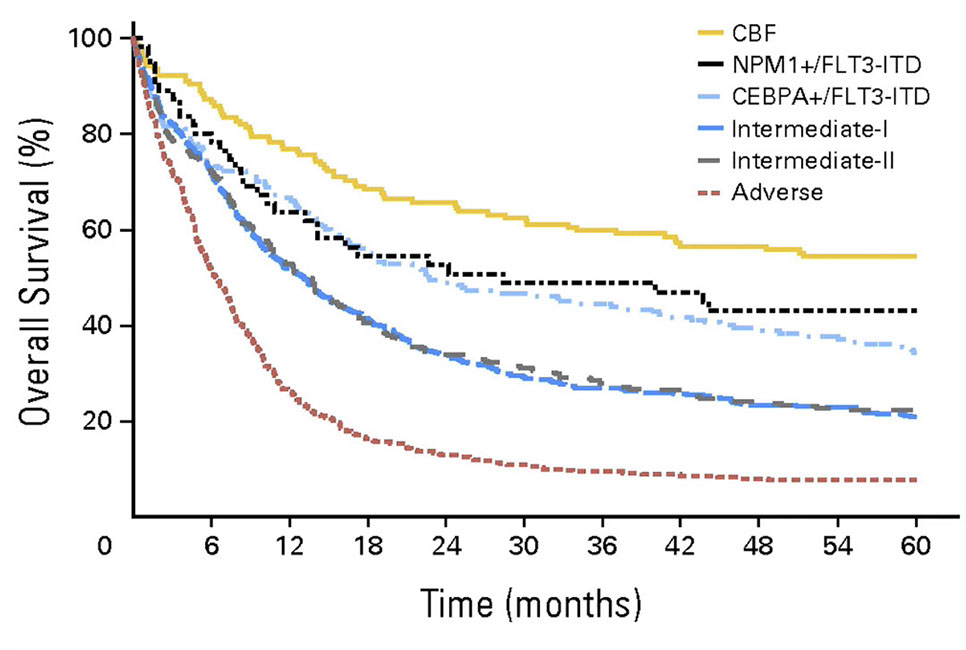

Acute Megakaryoblastic Leukemia

AML with BCR-ABL1

- Provisional entity, rare (<1% of AMLs)

- vs CML, less often splenomegaly, lower PB basophilia, fewer dwarf megs

This disease is a De novo AML in which patients show no evidence (either before or after therapy) of chronic myeloid leukemia

- Cases of mixed phenotype acute leukemia (MPAL) and therapy-related are excluded

- If another recurring genetic abnormality is present, that abnormality drives the final classification

Deletion of antigen receptors (IGH, TCR), IKZF1 , and / or CDKN21 may support a diagnosis of de novo disease

Tx: Patients may benefit from tyrosine kinase inhibitor therapy

AML with BCR-ABL1. Must exclude CML

AML with gene mutations

-

AML with mutated NPM1

– Favorable prognosis only in absence of FLT3 ITD mutation; 30% of AML

- secondary mutations include FLT3 and DNMT3A

Micro: strong association with acute myelomonocytic leukemia and acute monocytic leukemia (80-90% of acute monocytic leukemias have NPM1 mutation

- Multilineage dysplasia found in 74/318 (23%) de novo NPM1 mutated AML

- No significant survival difference of multilineage dysplasia in the presence of NPM1 mutation, a normal karyotype and no history of MDS

- Presence of NPM1 mutation trumps multilineage dysplasia

- secondary AML cases (arising from MDS, MPN, therapy related) lack favorable prognosis of de novo AML

__________________________________________

IHC: high CD33, variable (often low) CD13, usually positive for CD117, CD123, CD110

- negative HLA-DR and CD34 (CD34+ cases associated with a worse prognosis)

2 flavors described

1. Immature myeloid IHC profile

2. Monocytic profile (CD36+, CD64+, CD14+)

CD34+/CD25+/CD123+/CD99+ associated with FLT3 mutations